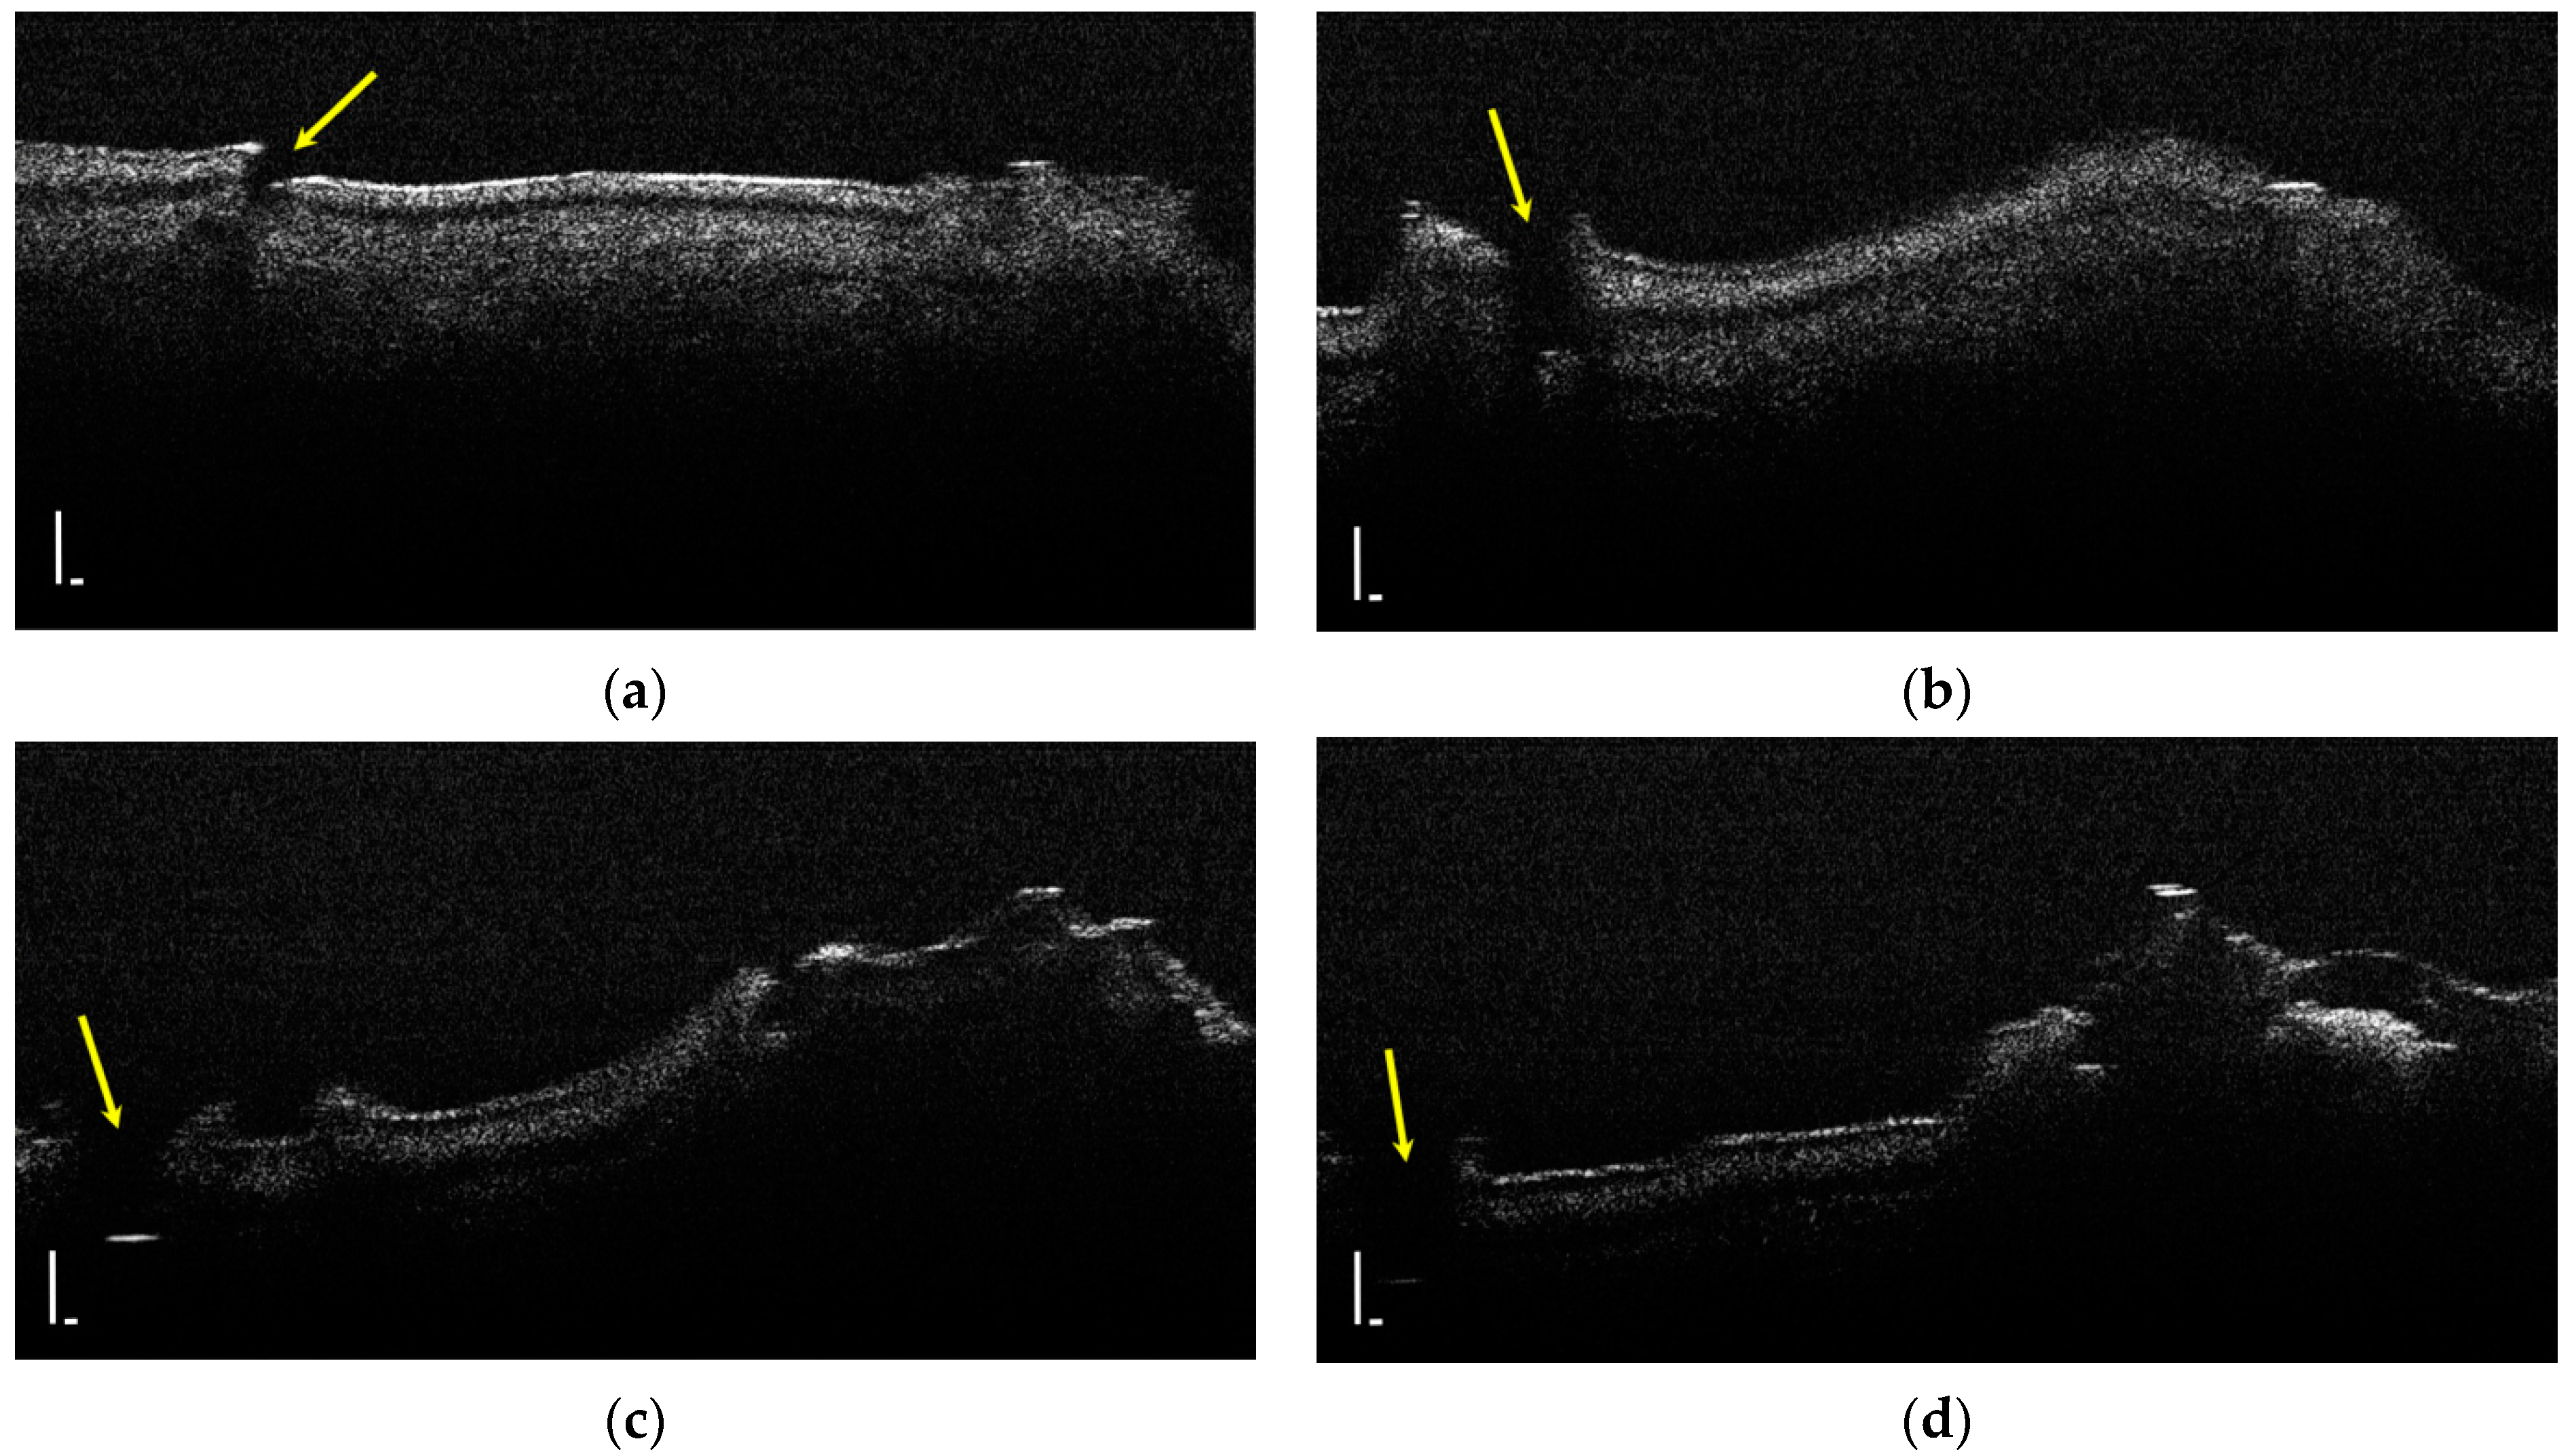

During the OCT examination of enamel defects, the hypomineralization was characterized by an intense, inhomogeneous OCT signal. In those areas, the enamel was demineralized; therefore, the image was diffuse (Figure 4).

Figure 4.

Two-dimensional OCT images of a tooth with hypomineralization (areas marked by yellow arrows): (a) cusp presenting a hypomineralization area; (b) extended area of hypomineralization, divided by a bridge of healthy enamel; (c) small-size hypomineralization area; (d) cusp presenting a hypomineralization area (scale bar 100 μm).